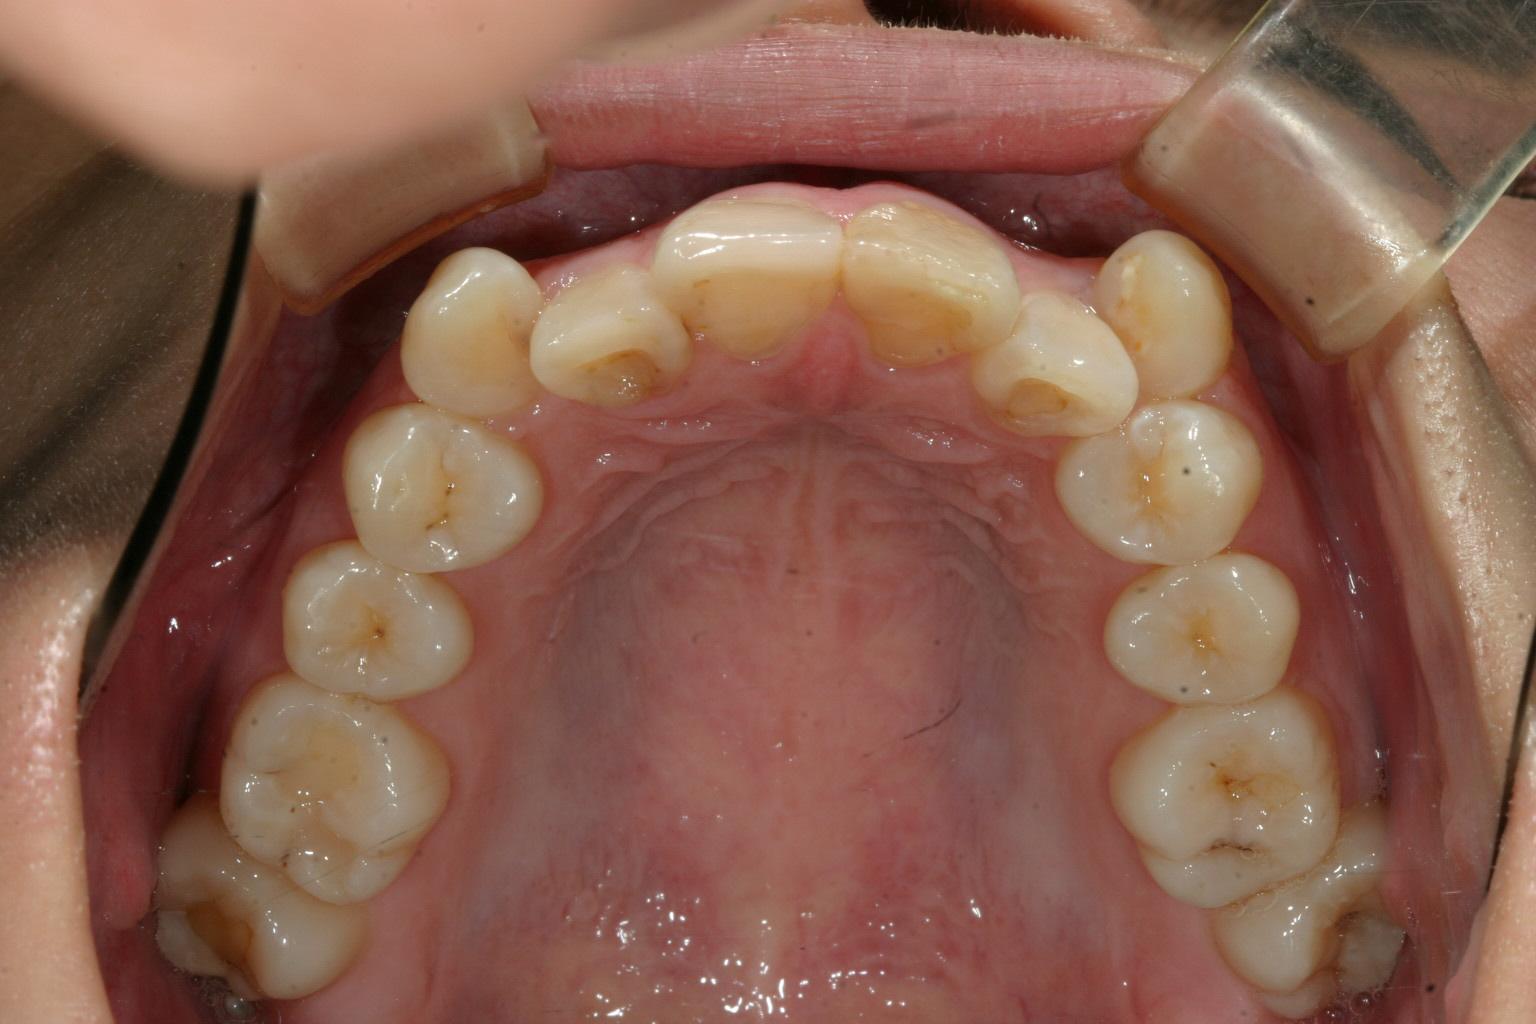

上の糸切り歯ですがかなり飛び出してます。

犬歯が飛び出してる関係で少し側面観も乱れてます。